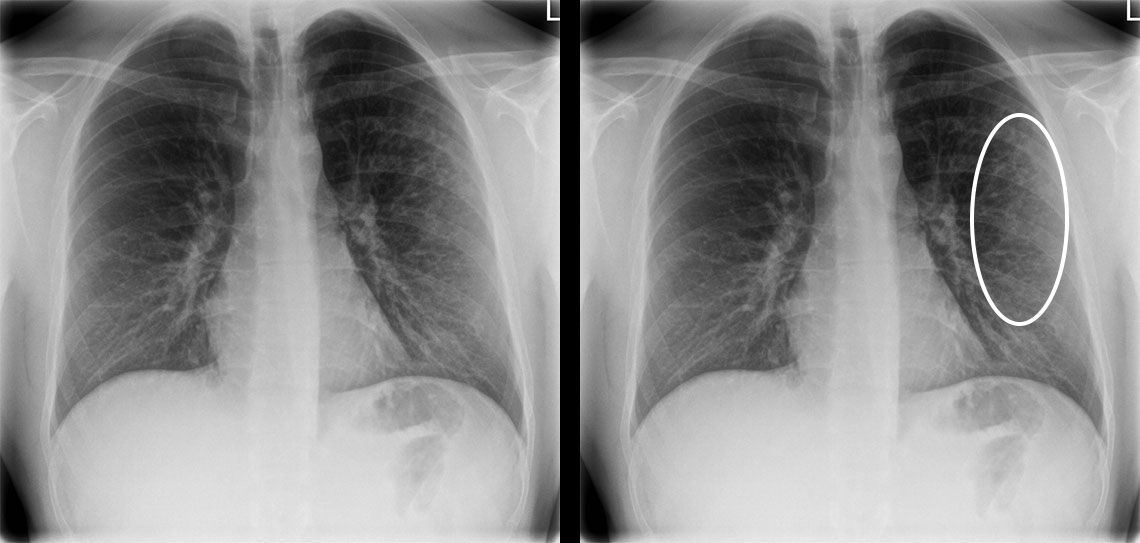

Atyyppinen pneumonia HIV-potilaalla.

Nuorella miehellä oli ollut 2 viikkoa yskää ja lämpöilyä. Potilaalla oli HIV, jota oli hoidettu asianmukaisesti. Keuhkoauskultaatiossa oli kuultavissa obstruktiota.

Thoraxröntgeniin kuvautui atyyppinen pneumonia. Distaalisessa keuhkoparenkyymissä on kauttaaltaan varjostumaa ja kuviolisää (ympyrä).